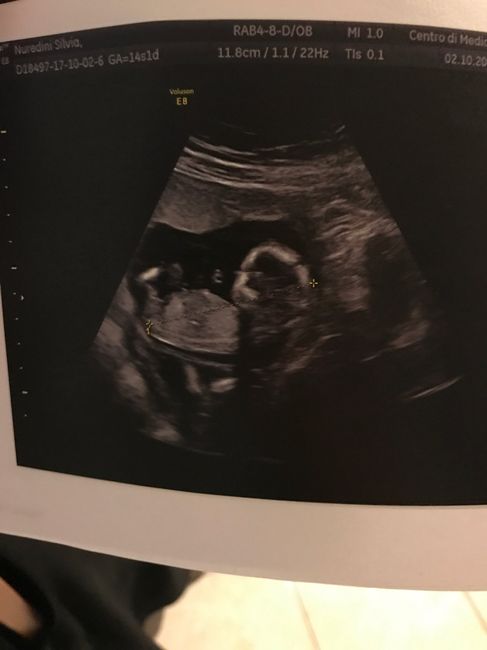

Ciao a tutte! Oggi ho fatto l'ecografia privatamente per togliermi i dubbi sulla differenza tra i bimbi ma effettivamente hanno una settimana circa di differenza, e oggi il ginecologo mi ha detto che secondo lui sono monocoriali biamniotici e non...